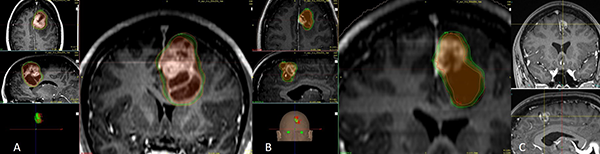

Los tratamientos con Infini™ fueron administrados a 28 (76%) pacientes, 19 (67%) de ellos en una sola fracción y 9 (32%) de ellos en protocolo de radiocirugía adaptativa, la dosis de prescripción para todo el grupo fue de 13.8 Gy (7.5-18Gy) a la curva del 50%, con dosis media en el PTV de 17.9 Gy (13.2-23.3Gy), con un volumen medio de 16.3 cc (8.5-78.4 cc). Para el protocolo de radiocirugía de dos sesiones la dosis de prescripción fue de 14.5 Gy (10-18) con una dosis media de 20.5 Gy (13.2-23-3) en la primera sesión a un volumen de 12.8 cc (8.5-78.4) y de 13.5 Gy (10-18) con una dosis media de 18.6 Gy (13-26) en la segunda sesión a los 30 días a un volumen de 4.3 cc (0.4-70) por efecto del tratamiento inicial y la consecuente reducción del tamaño tumoral (figs. 1 y 2).

Figura 1: A) Muestra una lesión metastásica de cáncer de mama en cerebelo izquierdo de 11.2 cc en volumen y se administraron 12 Gy como dosis marginal a la curva isodosica del 50% (Dosis media de 16.6 Gy). B) Segunda sesión a los 30 días en donde la lesión ha reducido su volumen a 4.9 cc representando una reducción del 56%, el efecto de masa sobre el cuarto ventrículo ha sido resuelto, se prescribió una nueva dosis de radiocirugía ahora con 15 Gy como dosis marginal a la curva isodósica del 50% (Dosis media de 19.7 Gy). C) A los tres meses la lesión mide 1.3 cc.